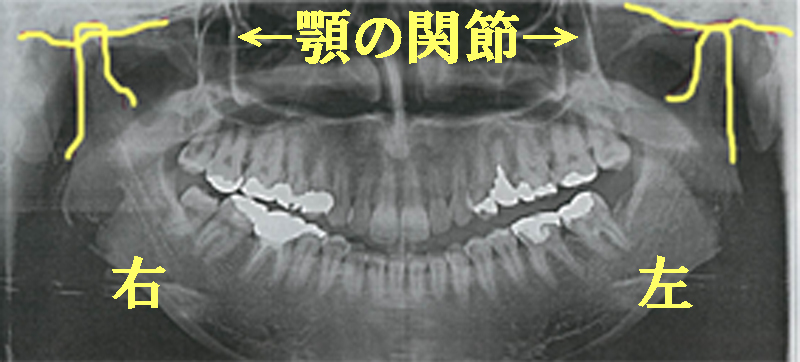

このパノラマレントゲン写真にうつっているのは歯と歯を支えている「骨」、そして左右の顎の関節全体です。鼻もうつります。

鼻の下あたりから顎、耳の下くらいまでの範囲と考えて下さいね。

歯科レントゲン写真でみる顎関節

パノラマレントゲン写真での顎関節の見方です。

左右の顎(あご)の関節をみてみましょう。

左右に黄色く記している部分が顎関節(がくかんせつ)、アゴの関節部分になります。

顎がカクカク音がしたり、顎が痛い、口が開きにくいといった症状がでている方は左右の顎関節がすり減っていたり左右が歪な形になっていることがありますのでこのパノラマレントゲン写真で確認することができます。